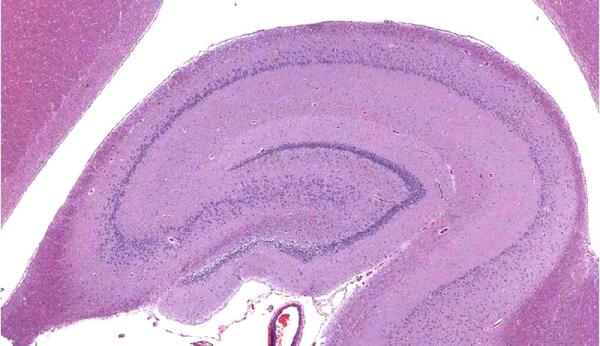

Потеря памяти, способности концентрации внимания, ориентации на местности и в виртуальной реальности, депрессия, слабоумие, некоторые формы эпилепсии, старческого маразма, идиотии — это все он в ретрограде. Когда он ссыхается, уменьшается в размере, тогда мы, как в старом анекдоте, забываем, что у нас эклер потому что у нас таки склероз. Объем гиппокампа естественным путем уменьшается с возрастом. Отсюда и «моменты возраста».

И вот он, третий аргумент. Из Северной Каролины. Вот что установили ученые: чем выше степень религиозности людей, тем меньше у них объем гиппокампа. И, следовательно, тем больше проявлений, связанных с усыханием этого участка проблем: сильнее деменция, депрессия, стресс, поражение абстрактного мышления, навигации и прочих радостей жизни.